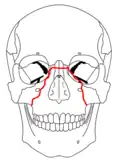

At the beginning of the 20th century, René Le Fort mapped typical locations for facial fractures; these are now known as Le Fort I, II, and III fractures (right).[7] Le Fort I fractures, also called Guérin or horizontal maxillary fractures,[14] involve the maxilla, separating it from the palate.[15] Le Fort II fractures, also called pyramidal fractures of the maxilla,[16] cross the nasal bones and the orbital rim.[15] Le Fort III fractures, also called craniofacial disjunction and transverse facial fractures,[17] cross the front of the maxilla and involve the lacrimal bone, the lamina papyracea, and the orbital floor, and often involve the ethmoid bone,[15] are the most serious.[18] Le Fort fractures, which account for 10–20% of facial fractures, are often associated with other serious injuries.[15] Le Fort made his classifications based on work with cadaver skulls, and the classification system has been criticized as imprecise and simplistic since most midface fractures involve a combination of Le Fort fractures.[15] Although most facial fractures do not follow the patterns described by Le Fort precisely, the system is still used to categorize injuries.[5]

| Le Fort I fractures | |